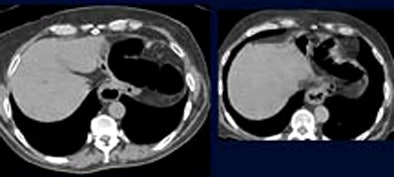

![]() |

| Gallstones constituted 10% of moderately important findings. All images courtesy of Dr. Franco Iafrate. |

| Hiatal hernias constituted 28% of moderately important findings. |